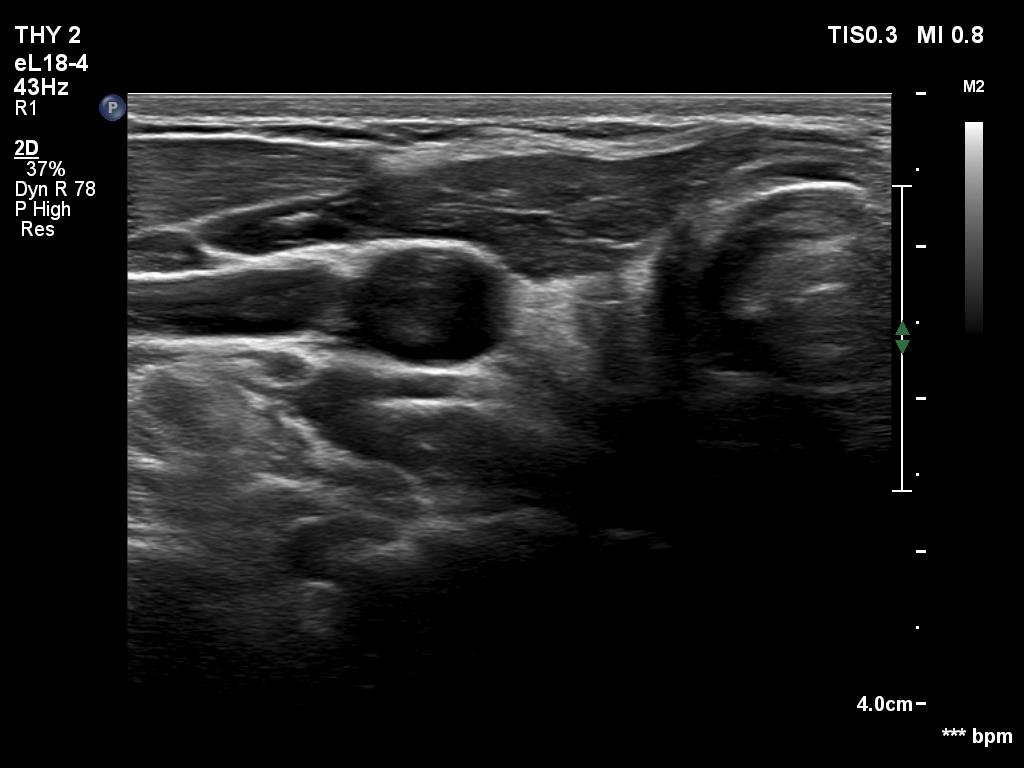

First examination (1st to third rows of images):

Clinical data: A 14-year-old boy was referred for evaluation of a nodule discovered by himself.

Palpation: a hard, not freely moveable nodule in the isthmic part of the left lobe.

Ultrasonography revealed a hypoechogenic nodule in the ventromedial part of the left lobe. The nodule had irregular borders, contained microcalcifications and displayed perinodular and irregular intranodular blood flow.